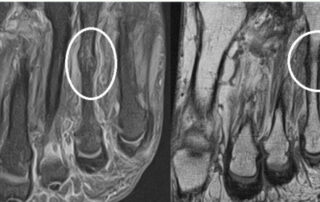

La suor durant els mesos de més calor pot provocar ampolles i fregaments als peus. Et comptem com evitar-les per no interrompre els teus entrenaments. La meva experiència com a podòleg esportiu fa que em trobi de manera habitual, amb l'arribada de la calor, a 'runners' amb lesions als peus. Les més freqüents són